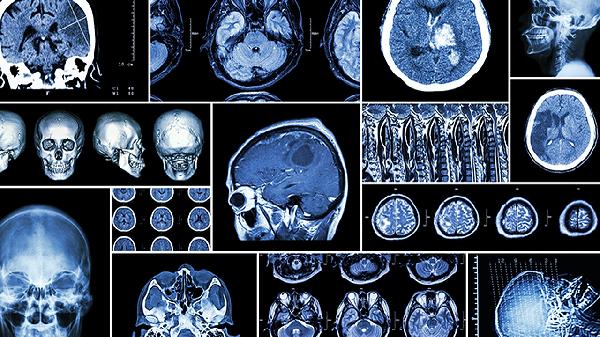

脑溢血急性期治疗以控制出血、降低颅内压为主,常用药物包括甘露醇注射液降低颅压,氨甲环酸注射液止血。恢复期治疗需结合肢体功能康复,可遵医嘱使用神经保护剂如胞磷胆碱钠片。血塞通片的使用必须由神经科医生综合评估出血吸收情况、血管状态及凝血功能后决定,不可自行用药。患者日常需保持血压稳定,避免剧烈活动,饮食以低盐低脂为主,定期复查头部CT观察血肿吸收情况。